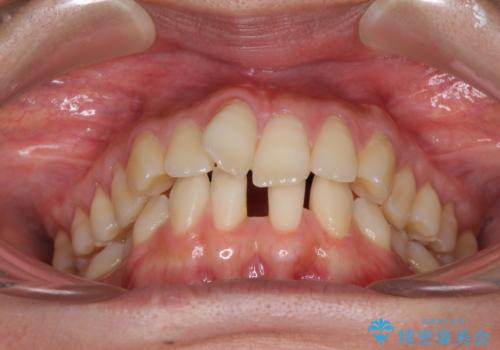

- 下顎前歯の欠損により隙間ができていることを気にして来院された患者様です。

下顎前歯が2歯欠損しており、スペースになっており、上顎は叢生歯列となってしました。